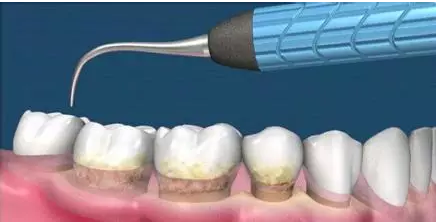

這是牙周病常規(guī)的治療方法,清除或控制臨床炎癥和致病因素,去除病因,消除炎癥。包括口腔衛(wèi)生宣教、充填齲洞、口腔潔治刮治、牙體牙髓治療、咬合調(diào)整、去除不良修復(fù)體、藥物治療(輔助手段,局部用藥效果好)、拔除治療效果不佳的牙周病患牙等。

牙周炎發(fā)展到一定階段時(shí),僅采用基礎(chǔ)治療難以取得較好療效,必須通過(guò)適時(shí)而合宜的手術(shù)治療挽救患牙,才能保持牙周組織健康,延長(zhǎng)患牙在口腔內(nèi)的壽命,維持牙列的完整性,促進(jìn)全身健康。其手段包括齦下刮治、根面平整、牙周翻瓣術(shù)、牙齦切除術(shù)、牙周夾板固定術(shù)等。